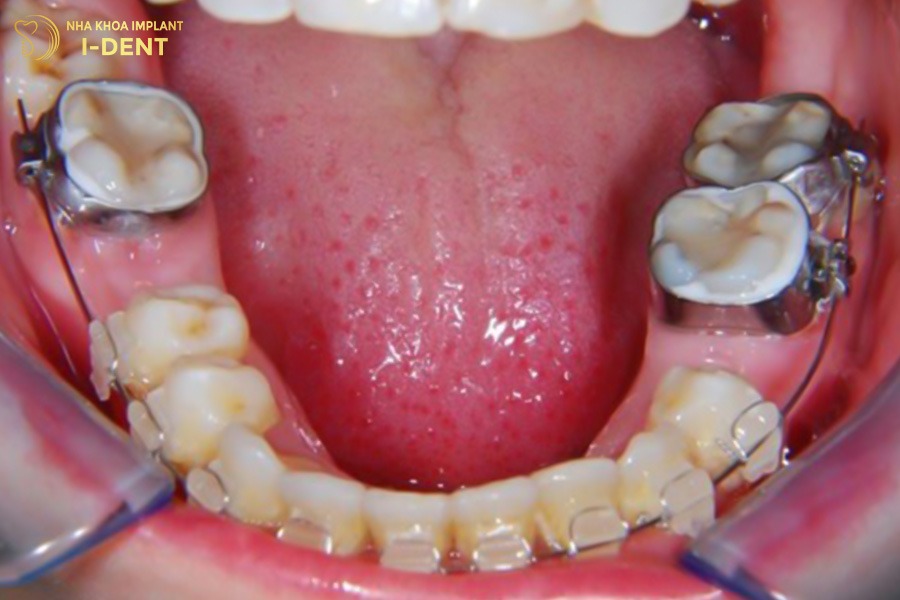

Mất răng hàm có thể niềng răng bằng cách sử dụng mắc cài để kéo các răng lân cận lại, lấp đầy khoảng trống mà răng hàm để lại. Tuy nhiên ca niềng sẽ có độ phức tạp cao, bác sĩ cần đánh giá tình trạng các răng xung quanh (đặc biệt là răng khôn) và xương hàm để lập phác đồ điều trị phù hợp. Bởi răng hàm tương đối lớn, có vai trò nghiền nát thức ăn nên khi mất đi sẽ để lại khoảng trống rộng và ảnh hưởng ăn nhai. Trong vài trường hợp, có thể phải cắm minivis để làm điểm neo chặn.